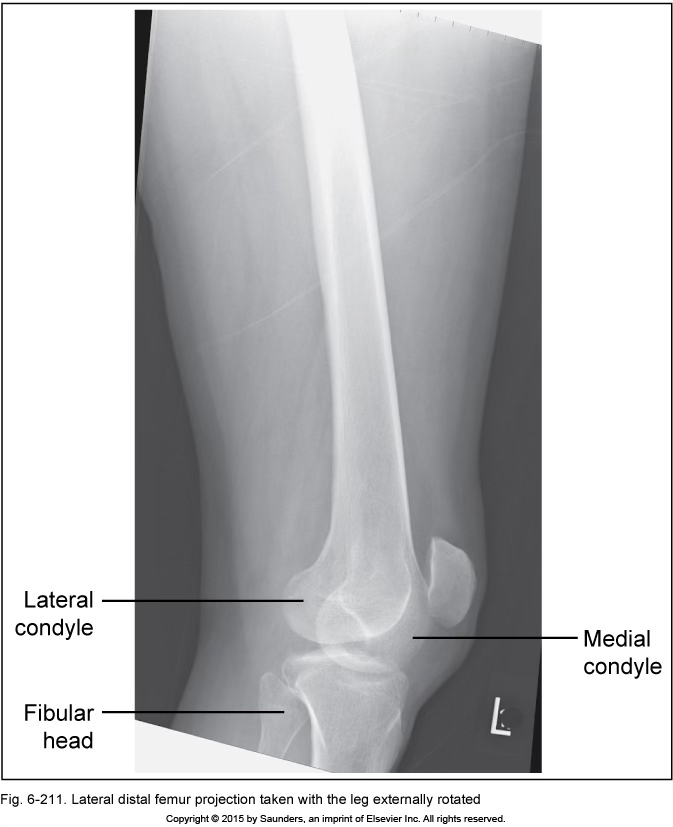

lateral femur

leg externally rotated